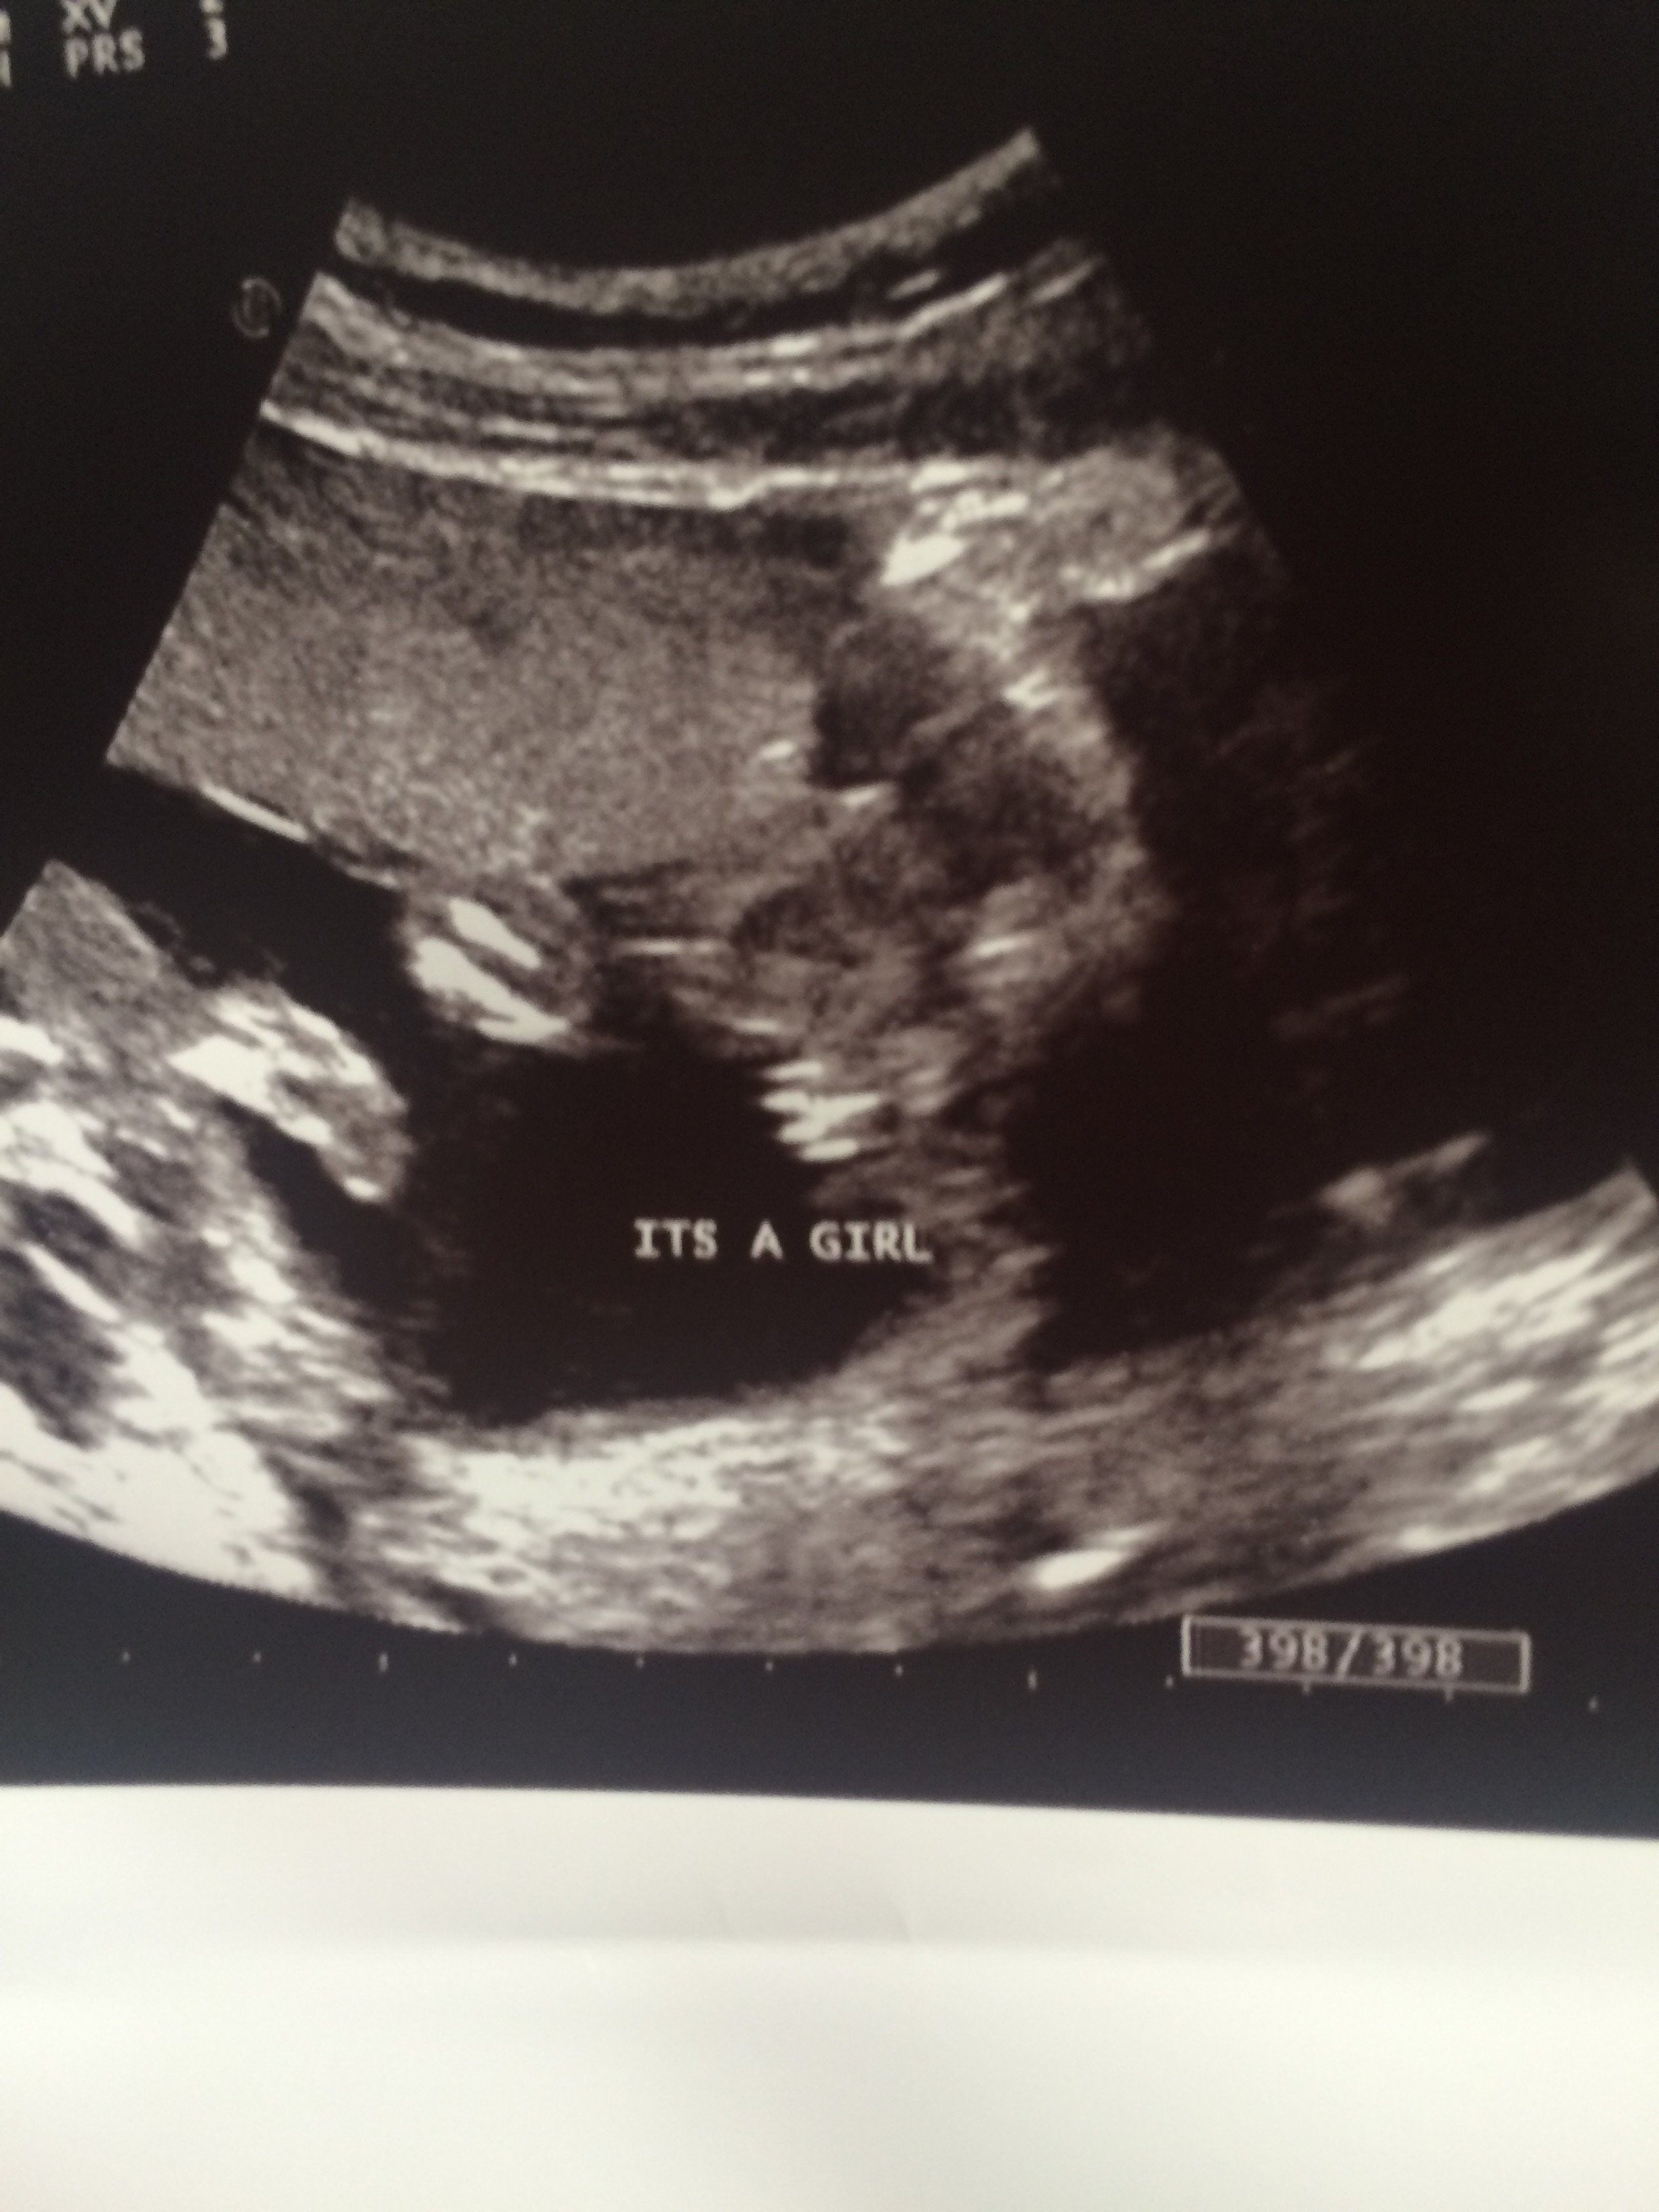

FTM - After a lot of rolling around baby girl revealed herself yesterday! And we get to go back in 3 weeks for another ultrasound because she would not show her spine. Stubborn like her daddy.

We had our scan yesterday! Baby girl, Violet Isabelle will arrive October 21 He big brother Lucas is not quite as excited as us yet (he had his heart set on a brother), but I think he is going to LOVE the big brother role!!

Just found out we are having a little girl!! Probably going to be Charlotte Faye, but not 100%. I just have this image in my head of reading Charlotte's Web to her in a few years.